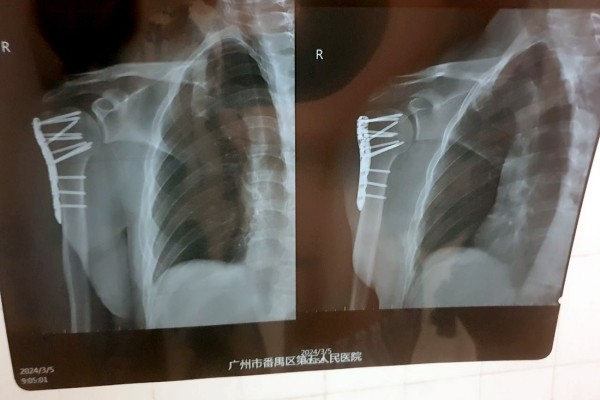

— Все это заняло около двух часов. Процесс не был приятным, так как я был в сознании и ощущал все манипуляции, проводимые на костях моего плеча, включая сверление, например. Была установлена пластина, которая зафиксировала поврежденные кости в правильном положении. После операции побочных эффектов не было, однако в течение еще шести часов врачи подключали различные датчики для контроля состояния. Все это время нельзя было есть и пить. А рука ощущалась как кусок бревна, — вспоминает читатель.

— Китайские врачи проделали по-настоящему хорошую работу. Это подтвердил знакомый белорусский хирург, взглянув на мои послеоперационные снимки. Думаю, не последнюю роль в этом сыграло и то, что я иностранец: мне показалось, что врачи особенно старались сделать все по высшему разряду. Также это хороший пример того, что надо смотреть не на вывеску больницы. Главное — это именно врачи и их отношение к своей работе, — считает молодой человек.

Белоруса выписали из больницы спустя три дня после операции. Впереди длительная реабилитация и еще одна операция — для того, чтобы изъять из плеча металлическую пластину.